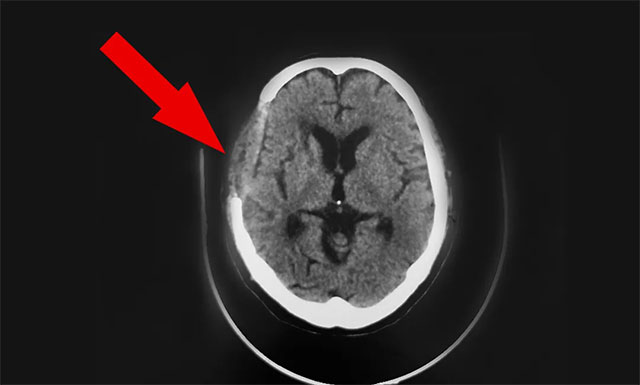

近期,因头晕不适感持续,前往上海某医院就诊检查。行头颅CT发现:1. 两侧半卵圆中心区及基底节区多发腔隙性脑梗塞;2. 左小脑及右侧基底节区斑片软化灶;门诊拟以“颈内动脉狭窄、脑梗死”收入。治疗一个月后无明显改善。为求进一步治疗,9月中旬胡夫人陪同患者胡某慕名转往上海蓝十字脑科医院,由6B神经外科潘仁龙主任接诊。

在潘仁龙、吴志群及黄秀夫三位医生会诊下,基于患者近半个月主诉有头晕,偶有行走不稳,头晕症状明显,次数较前明显增加。9月16日CT头颅CTA+CTP 示病患右侧大脑中动脉M1段、左侧大脑后动脉多处狭窄,右侧大脑中动脉中央、远端分支明显稀疏、减少等;考虑心脏支架术后状态,基础性疾病较多,颅内多发血管性狭窄,行血管搭桥手术风险较高,建议行颞肌贴敷术,以改善患者病情,提高患者生活质量,建议尽早手术治疗。